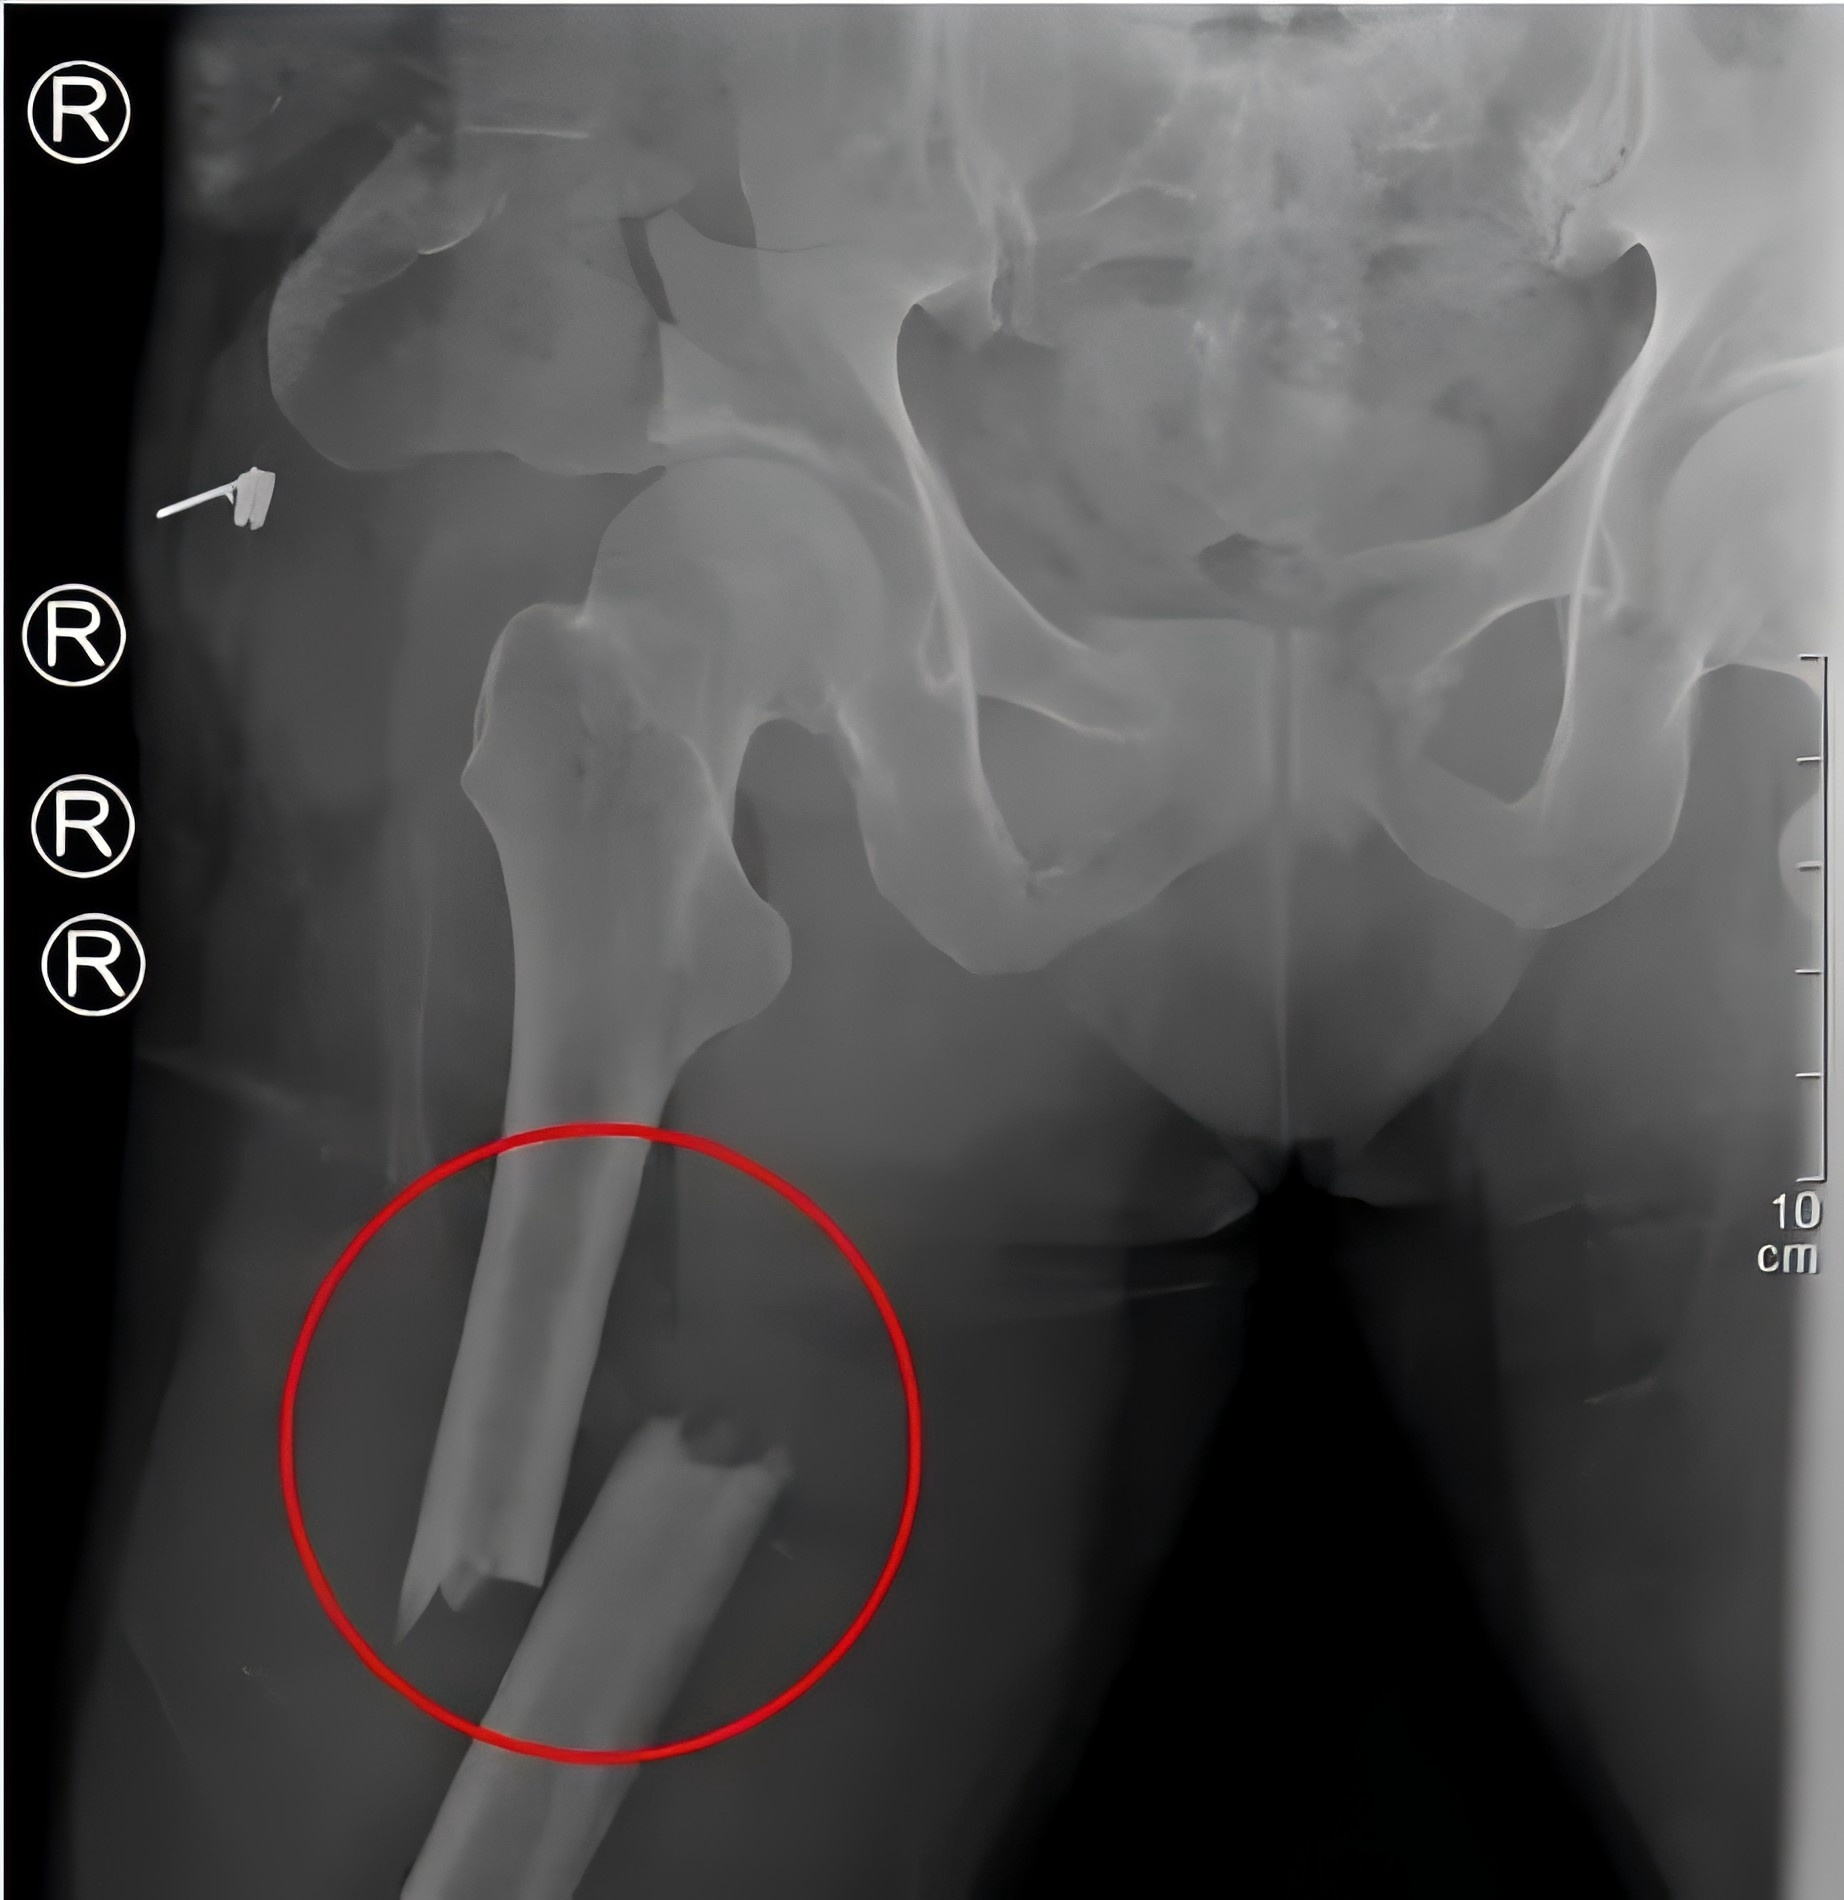

全力以赴救治重傷患者

2月28日,48歲的戴某不慎被重物(重量約為2噸)砸傷,導致多發(fā)性骨盆骨折、右側(cè)粉碎性髂骨骨折、雙側(cè)股骨骨折、右側(cè)腓骨骨折等多處損傷,尤其是骨盆處幾乎“散架”,患者失血性休克,生命垂危。

殷小軍團隊基于損傷控制理念,為患者量身定制了微創(chuàng)手術(shù)方案。手術(shù)分為兩期進行:待患者生命體征穩(wěn)定后,一期先行骨盆及一側(cè)股骨骨折微創(chuàng)內(nèi)固定治療;二期行另一側(cè)股骨骨折微創(chuàng)內(nèi)固定手術(shù)。

(患者術(shù)后X片)